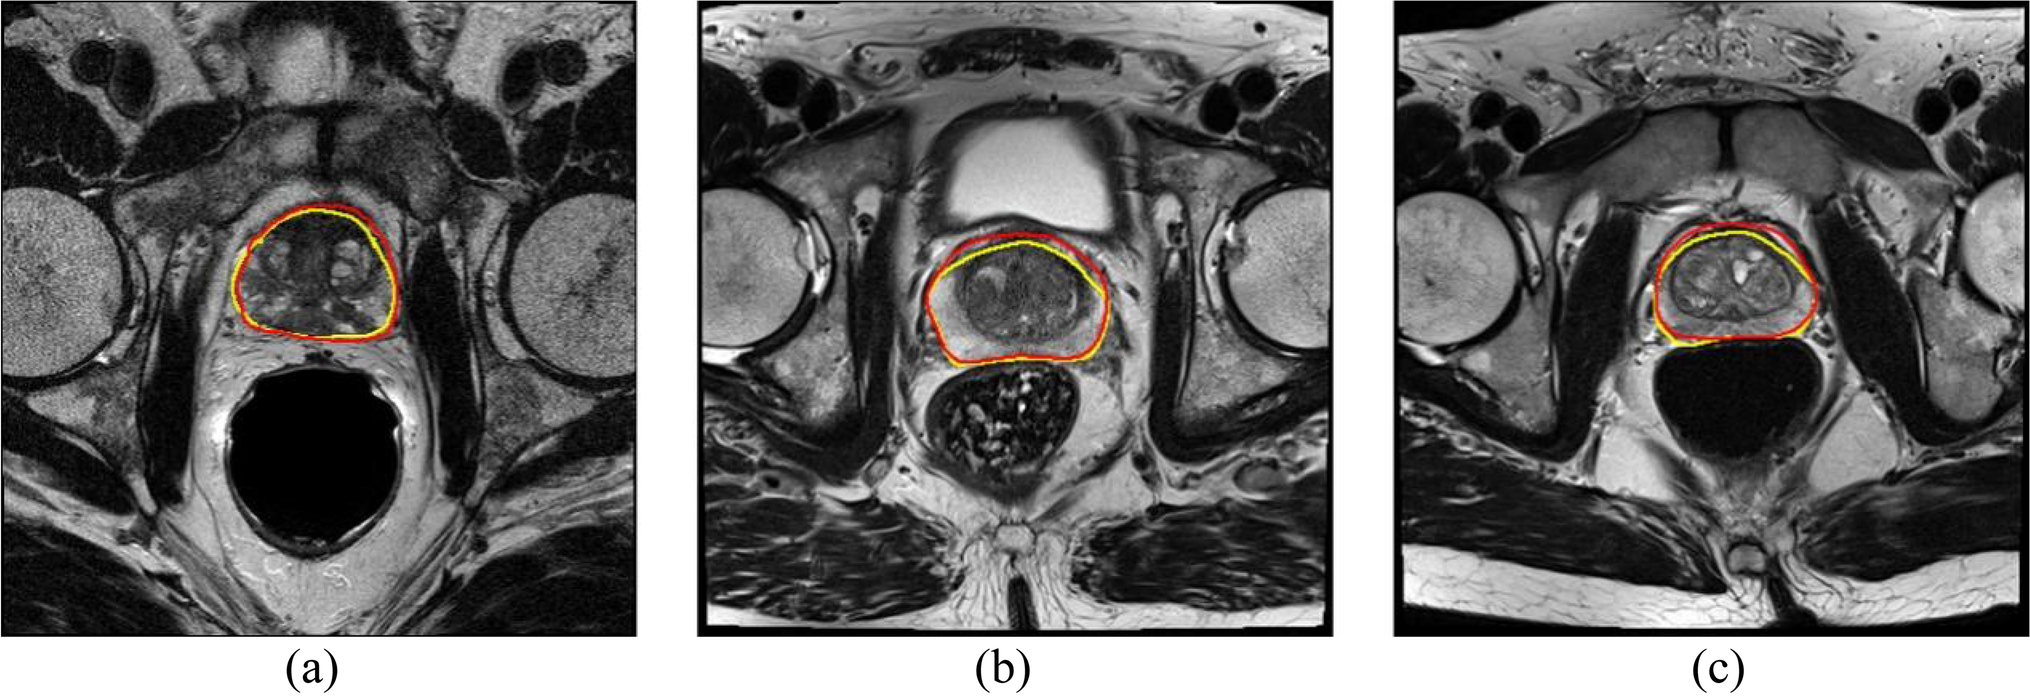

Compare with other prostate segmentation methods: CNN based method [31], Super Voxel-based method [32], U-net [18], R2U-net [33], Att U-net [34] and U-net +  + [21]. U-net, R2U-net, Att U-net and U-net +  + are reproduced through the article. The hyper-parameters of the above models are basically the same, such as the learning-rate is set to 1e-4, the epoch is set to 25, the batch-size is 4, all use Adam with Momentum optimizer. The accuracy results of other methods are derived from the corresponding papers. The comparison of the segmentation accuracy is shown in Table 1. The proposed method obtains a competitive result among the fully automatic segmentation algorithms. Figure 4 shows the segmentation results.

Fig. 4

Results of prostate image segmentation, where the yellow contours are the gold standard and the red contours are the algorithm segmentation result

We used the three types of medical images to verify the performance of the segmentation algorithm based on our method. The steps are as follows: First, we preprocessed the training image, including uniform image size and grayscale normalization. Second, we used the statistic shape model and 3D thin plate spline to achieve the purpose of data augmentation. Third, we constructed the medical transformer network structure to segment three types of medical images. The test results show that the segmentation algorithm proposed in this paper achieved a DSC of 89.97%, 91.90%, and 94.25% on the prostate MR images, heart US images and tongue color images, respectively.